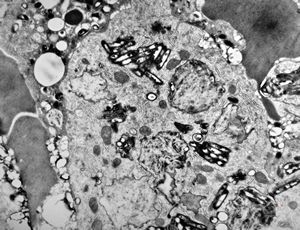

Whipple disease